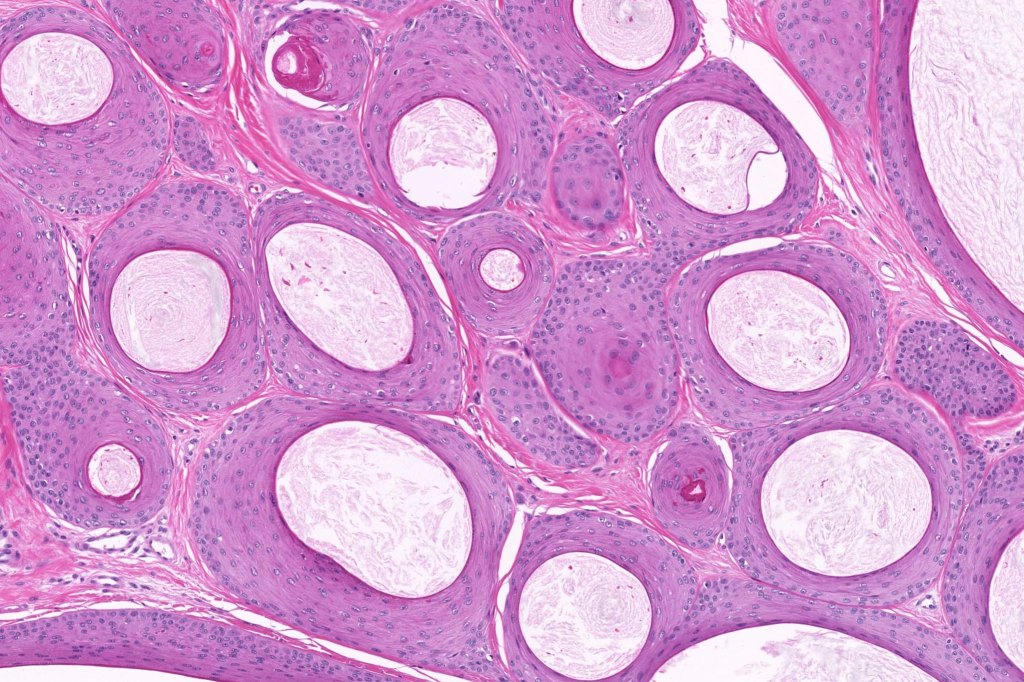

•Keratocysts showing infundibular keratinization i.e.with a granular cell layer

•Solid epithelial islands

•Fibrovascular stroma